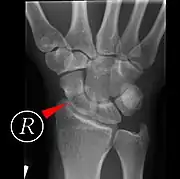

Scaphoid fractures may be difficult to diagnose via plain x-ray. A repeat x-ray may be required at a later date, as might cross-sectional imaging via MRI or CT scan.[6]

Fractures of the scaphoid are the most common of the carpal bone injuries, because of its connections with the two rows of carpal bones.[1]: 177

The scaphoid can be slow to heal because of the limited circulation to the bone. Fractures of the scaphoid must be recognized and treated quickly, as prompt treatment by immobilization or surgical fixation increases the likelihood of the bone healing in anatomic alignment, thus avoiding mal-union or non-union.[6] Delays may compromise healing. Failure of the fracture to heal ("non-union") will lead to post-traumatic osteoarthritis of the carpus.[1]: 189 One reason for this is because of the "tenuous" blood supply to the proximal segment.[3] Even rapidly immobilized fractures may require surgical treatment, including use of a headless compression screw such as the Herbert screw to bind the two halves together.

Healing of the fracture with a non-anatomic deformity (frequently, a volar flexed "humpback") can also lead to post-traumatic arthritis. Non-unions can result in loss of blood supply to the proximal pole, which can result in avascular necrosis of the proximal segment.